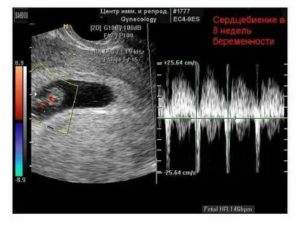

На шестой (акушерской) неделе беременности пульсация маленького сердечка становится четче, интенсивней. Первая пульсация уже однокамерного сердца проявляется к 26 дню (5 недель) жизни ребенка.

Благодаря УЗИ сердцебиение у плода можно определить уже на 5-6-ой акушерской неделе беременности. Развитие плода проходит хорошо если сердцебиение слышно и оно в пределах нормы. Если его не зафиксировали можно провести повторное обследование примерно через неделю или применить другие методы диагностики.

Итак, с шестой недели беременности можно увидеть и измерить биение на экране монитора. Прослушивается сердцебиение плода уже с пятой недели, особенно если УЗ-оборудование имеет хорошую мощность.

Трансвагинальный датчик обнаруживает сердечную деятельность с пятой недели, трансабдоминальный – не ранее, чем с шестой.

Впервые биение сердца малыша можно услышать приблизительно на сроке 6 недель. В это время длина плода достигает около 6 мм. На этом сроке оно уже сформировано, но развито оно еще не окончательно.

На этом сроке, на ультразвуковом исследовании еще невозможно увидеть сердечко малыша, так как оно еще слишком маленькое. Зато можно первый раз прослушать, как оно стучит.